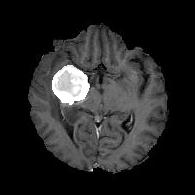

(a) (b) (c) (d)

Boundary Stream:

Fig. 2 demonstrates the output of each of the attention layers in our dedicated boundary stream. In essence, each attention layer progressively localizes the tumor and refines the boundaries. The first attention layer has learned rough estimate of the boundaries around the tumor and localized it, whereas the second and third layers have learned more fine-grained details of the edges and boundaries, refining the localization. Moreover, since our architecture leverages a dilated spatial pyramid pooling to merge the learned feature maps of the regular segmentation stream and the boundary stream, multiscale regional and boundary information have been preserved and fused properly, which has enabled our network to capture the small structural details of the tumor.